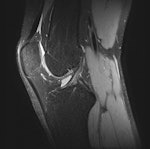

The 3D protocol consisted of a single 3D TSE acquisition in the sagittal plane with the SPACE sequence. The SPACE isotropic source data were postprocessed on a workstation (Leonardo, Siemens Healthcare) to create sagittal, coronal, and axial multiplanar reformatted (MPR) images with 1-mm slice thickness. Readers were free to use volumetric data to create MPRs in any orientation and slice thickness, they stated.

Accuracies were calculated using arthroscopy as reference standard. McNemar's test (p < 0.05) was used to compare 3D and 2D techniques. The highest diagnostic yield was obtained by the third reader (accuracies ≥ 88%). For the medial meniscus, readers performed better with the 2D technique than with 3D SPACE (accuracies 85%-88% versus 78%-80%, respectively) (p > 0.05). For the lateral meniscus and ACL, 3D and 2D techniques had similar performance (accuracies ≥ 93%). For cartilage lesions, 3D SPACE had significantly lower specificity than the 2D protocol for one reader.